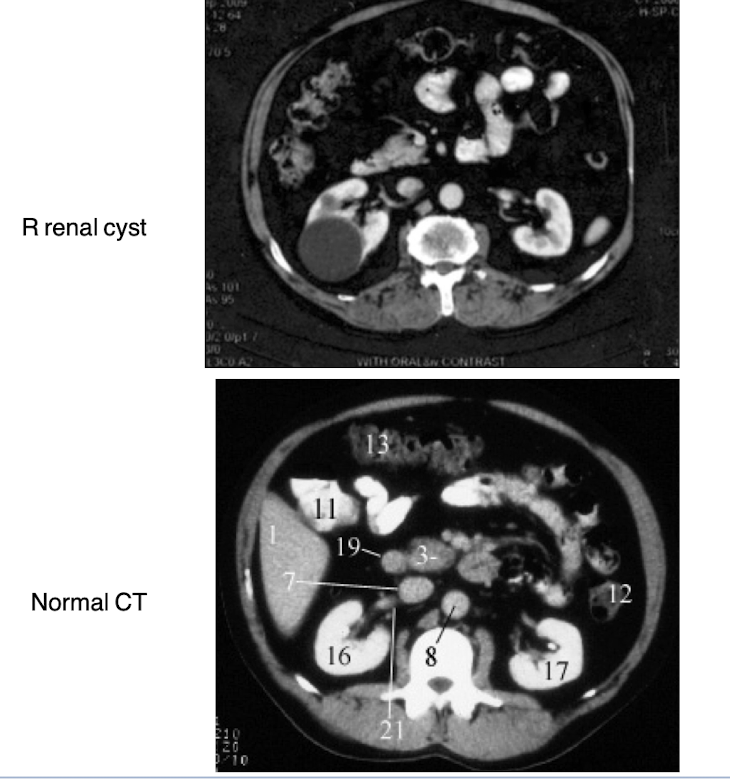

Identify the parts of the GI tract with CT imaging

What is occurring in the CT scan?

Acute cholecystitis - enlarged gallbladder

Differentiate between renal cysts and renal carcinoma including characteristics, how they appear when imaged.

Renal cysts are typically simple, fluid-filled sacs that are asymptomatic and have thin walls, while renal carcinoma presents as a solid mass with irregular borders and may show enhancement on imaging studies. Cysts appear anechoic on ultrasound, whereas carcinomas are often hypoechoic and may display vascularity on Doppler imaging.